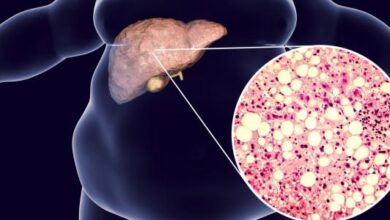

- الكشف عن البيليروبين: فوجود البيليروبين (بالإنجليزية: Bilirubin) في البول قد يدل على تعرض الكبد للتلف أو إصابته بأحد الأمراض والمشاكل الصحية.